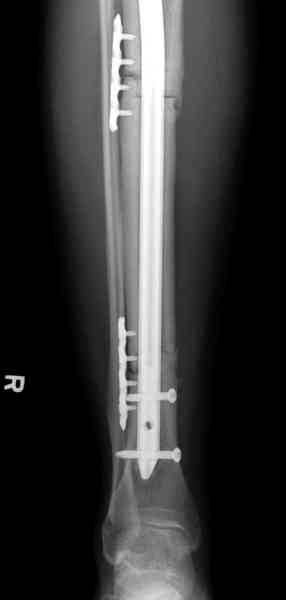

Жесткая Фиксация по три шурупа на сегменте удержат нагрузку на конечность.

Нет. Просвет внутри кейджа - 13 мм, штифт - 12 мм. Не так там и много пространства то есть. Но вопрос правильный, интересный, из разряда современных нерешенных проблем.

Не оригинальное, подход не раз был демонстрирован нас в стране проф. Анатолием Федоровичем Лазаревым (ЦИТО), который это называет "металлокаркасная пластика". У нас в институте в другом отделении он

помогал сделать несколько таких металлокаркасов, только, насколько я помню, без блокируемых стержней. А в мире эта методика довольно давно

применяется, хотя и не массово. Например, осенью прошлого года на конференции общества Кюнчера в Страсбурге было хорошее сообщение на эту тему. 17 больных, результаты уже до 5 лет.

The cages are commercially available but up to 10 cm. So we measured the needed length on x-rays, added 2 cm at both ends for sure that

the resected piece will include all, and resulted with 15 cm which one was ordered and individually made by the same factory. So yes, we made the gap to fit the cage.

The inner diameter of the tube is 13 mm, the nail was 12 mm, so not so much space to put something inside. Yes, this is really shaft endoprosthesis which i hardly ever would offer for a young football player. Though... Maybe we would when we collect some experience with this sort of implants to feel/prognose its strength in different settings.